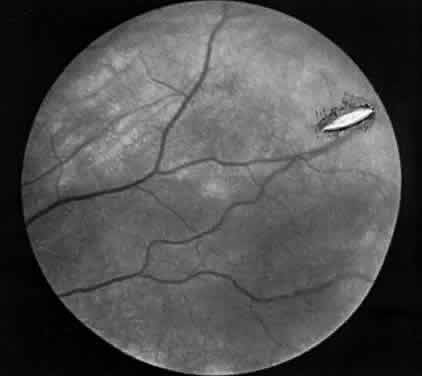

RETINAL PERFORATION DURING SURGICAL MANAGEMENT OF STRABISMUS

Hemorrhage initially covers the perforation site. Some of this hemorrhage may break through into the vitreous cavity but usually remains confined to the choroid and retina. In a day or two, bare sclera becomes visible, usually surrounded by residual hemorrhage and a rim of light pigmentation.19 It appears as if the choroid and the retina were scooped out, leaving bare sclera behind (Fig. 1). Inverted cutting needles seem responsible since this is a complication almost unheard of before or after their common use. Prophylaxis indicates the use of a needle that is not sharp on the convex curve. The management of these perforations remains controversial.20 In our experience, widely dilating the pupil permits nearly immediate diagnosis as the area can be clearly seen through the usually clear media. Depending on the characteristics of the perforation, transpupillary laser coagulation or direct cryotherapy can be administered easily. Some suggest, however, that observation without treatment is all that is required since the perforations are almost always self-sealing and result in no significant sequelae. Nevertheless, in a series of 728 patients with known scleral perforations, 14 (2%) of the cases had a retinal detachment and eight resolved without complications.21

Fig. 1. Scleral perforation several weeks after muscle surgery. (Schlaegel TF Jr: Essentials of Uveitis. Boston: Little, Brown, 1969:290.)